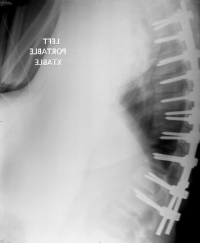

(Click to Enlarge Image) This is a post-operative X-ray of the results of a scoliosis surgery. Here you can see that the black line is the new center of gravity line for this patient. She is balanced and can walk without aids. The rods and screws seen are a temporary scaffolding to hold the patient in line while the fusion takes place. After solid fusion, the metal is superfluous.